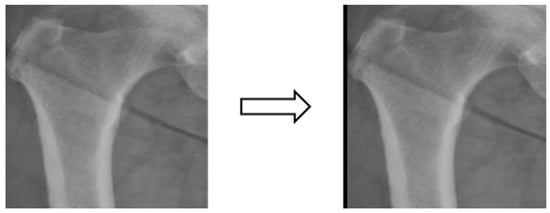

In this study, four parts of the image labeled X-ray images were used in image segmentation by feeding them into U-Net and U-Net++ models for training, and the bit depth of the four parts of the image was converted from the original 24 bits to 8 bits before the model training. The reason for choosing to use U-Net and U-Net++ is that their model structure is simpler, they do not need to spend a lot of time filtering out the remaining noise in the medical images, and they are less likely to form overfits for a small number of image datasets. The binary segmentation prediction results obtained after training the models of U-Net and U-Net++ are shown in Figure 3 below.

Figure 3. Image segmentation.